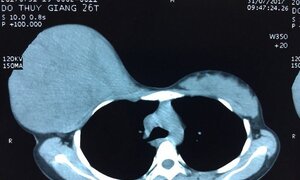

Người đàn ông phải cắt bỏ một phần phổi do 30 năm nghiện thuốc lá

Người đàn ông 56 tuổi hơn 30 năm nay mỗi ngày hút gần 40 điếu thuốc, vừa nhập viện Bình Dân với thương tổn phổi trên nền tai biến.